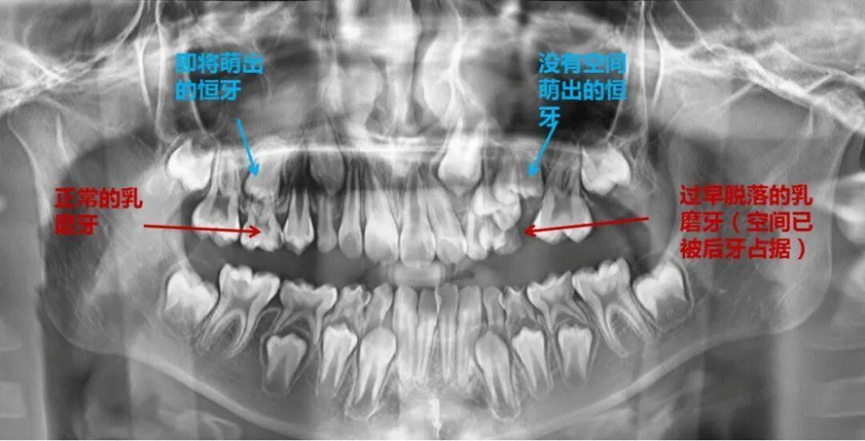

危害二:乳牙被蛀缺失掉,空出来的位置势必要会被其他的牙挤占,导致这个位置上的恒牙没地方长出来,只能长歪。

以下是乳牙期及替牙期常见的问题,很容易引发错颌畸形。

以后的恒牙被推挤得异位萌出,不在自己应该长得地方长出来,很容易变得东倒西歪、乱七八糟;